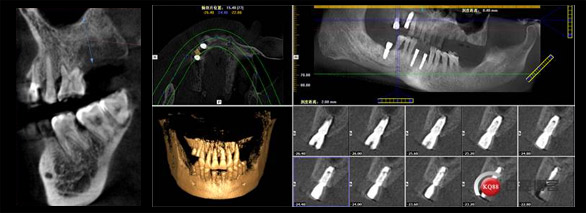

CBCT锥形束CT

360度旋转扫描即得患者骨量信息、软组织信息、咬合关系等头部完整数据,重组三维立体图像,超高清低辐射,医生可从任意角度观察分析病例。

数字化种植牙方案设计

整合患者口内的CBCT数据及咬合关系,将完整数据上传到会诊系统中,与数据库内数万病例进行综合对比、分析,规避术中并发症,模拟手术过程及预测术后治疗效果,以数字化全息影像为基础的方案设计对于患者来说更形象、更易懂,患者参与度更强。